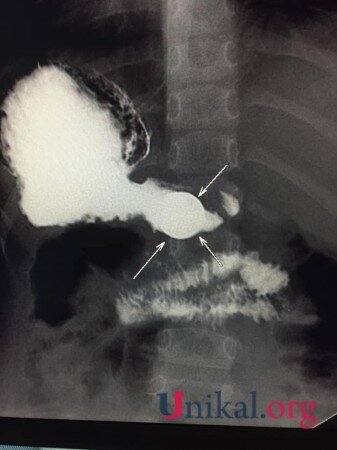

“Bir həftə qabaq 4 yaşında uşaq 5 qəpik udub. Bir həftədir qəpik uşağın mədəsindən ifraz olunmur. Gətiriblər müayinəyə, biz də aşkar etdik ki, qəpik hələ mədədir. Mədənin çıxacaq hissəsi uşaqlarda dar olduğuna görə çıxmır. Qəpiyin diametri mədənin çıxacaq hissəsinin diametrindən iki dəfədən çox böyükdür. Ona görə mədədən keçmədi, qalıb mədədə. Biz məsləhət gördük ki, endoskopiya müayinəsindən keçsin, endoskopik yolla çıxartsınlar. Hələ bir xəbər yoxdur. Qəpik uşağın mədəsindən çıxarılacaq”.